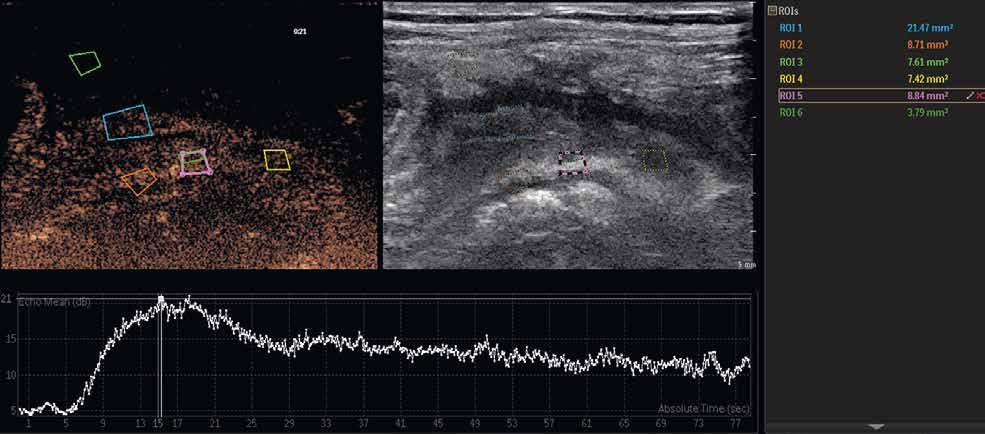

Při vyšetření střev by měl být mechanický index nižší než 0,1. Využíváme lineární sondy o frekvencích 7,5–12 MHz. V závislosti na použité sondě aplikujeme také množství kontrastní látky, obvykle okolo 3 ml. Výhodou je, že s odstupem několika minut lze kontrastní látku použít znovu, například na jiném patologicky změněném úseku střeva. Po aplikaci kontrastní látky sledujeme při duálním zobrazení sycení postiženého úseku střeva. Jde o dynamické vyšetření, během něhož pořizujeme videozáznam, který můžeme kvantitativně zpracovávat pomocí dedikovaných softwarů. Následným postprocesingovým zpracováním získáme křivku sycení, která může napovědět, o jakou fázi IBD se jedná (obr. 1–3).

Obr. 1–3: CEUS. Pacient s Crohnovou nemocí ve fázi aktivního zánětu. Po podání kontrastní látky je patrné postupné sycení střevní stěny (1, 2, levá část obrázku), která je výrazně zesílená s akcentovanou hypoechogenní sliznicí (1, 2, pravá část obrázku). Křivka sycení pak svědčí rovněž pro akutní fázi zánětu (3).